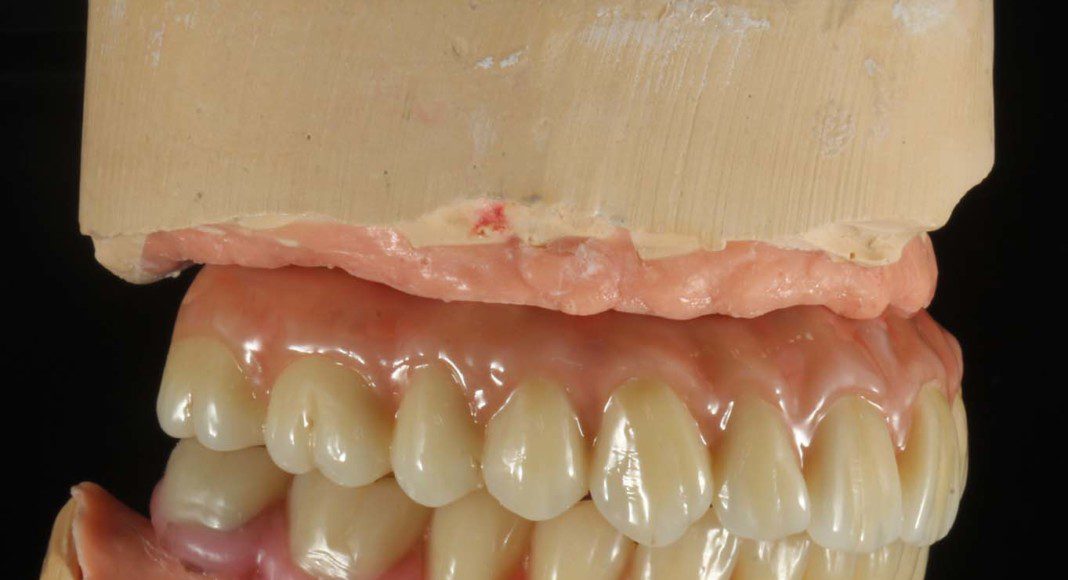

Even in the wax-up you can see the convex contour of the part of the prosthesis that touches the tissue. This is of paramount importance for cleaning. The visible cylinders are the connection to the implants. Frontal view with slightly superior angle.

Upper and lower wax try-in. Here we test the aesthetics, tooth display and bite. If there is any compromise, concern, or large bite discrepancy, we make notes, take pictures and a new bite and schedule another try-in. We do as many try-ins as necessary to make sure everyone is happy. After the wax try-in is approved, nothing can be changed.

Close-up occlusal view to show the slight crowding of the front teeth. Of all the things we do to make teeth look natural, slight crowding is the best technique. You will notice in the final smile pictures that you cannot tell there is crowding, just a really beautiful, natural smile.